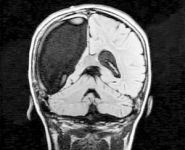

9-летняя жительница Бостона по имени Кэмерон поставила в тупик врачей и ученых. Всего за несколько недель, девочка смогла прийти в себя после сложнейшей операции по удалению правого полушария головного мозга.

В течение долгого времени малышку мучили судороги и тяжелые, едва ли не ежедневные, приступы эпилепсии. В конце концов, врачи вынуждены были удалить ребенку правое полушарие, которое отвечает за чувства, эмоции и ориентацию в пространстве.